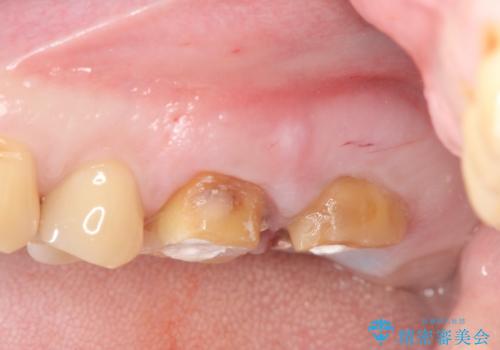

- 半年前から奥歯から嫌な臭いがする、と治療を求めて来院されました。

銀歯を除去したところ、虫歯が大きく再発しこのままではかぶせ直しができないような状況でした。